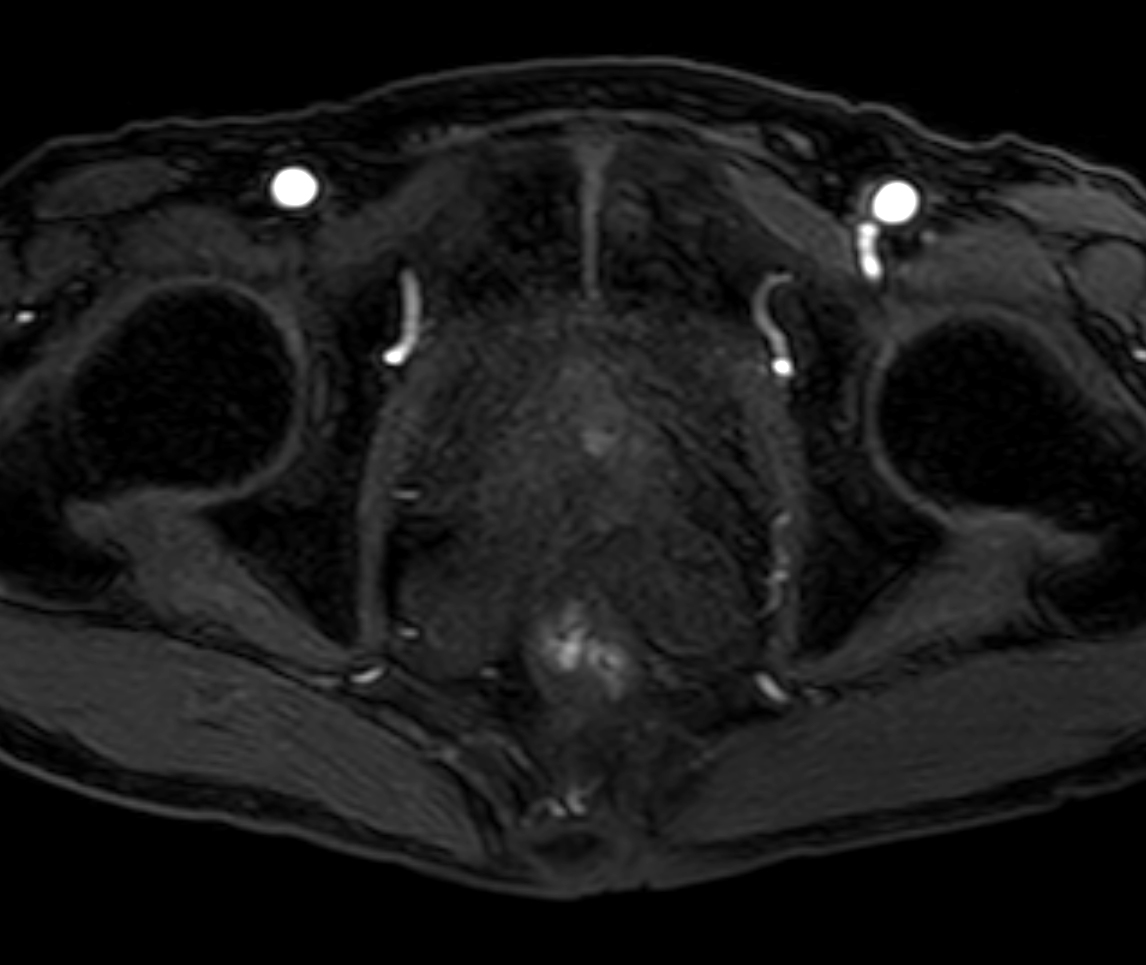

Axial DWI (b1000, ADC)